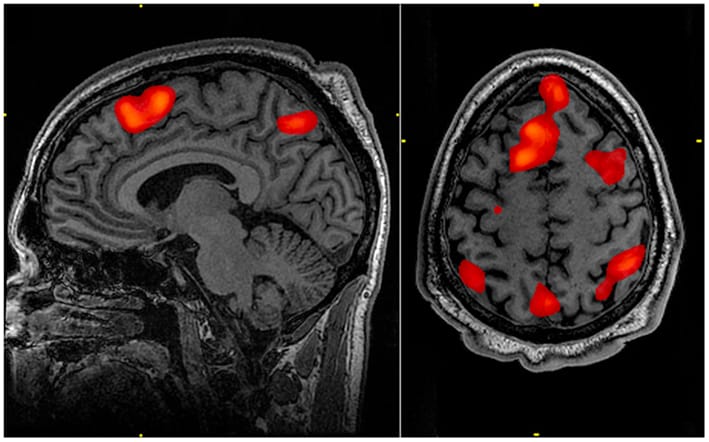

羅森堡的團隊想要找出「腦指紋」跟注意力之間的關係,因此,他們使用功能性磁振造影(註1,fMRI,全稱為functional magnetic resonance imaging)觀察 25個人在做無聊乏味的事情時,他們的大腦有什麼樣的活動。這 25個人要看著螢幕秀出一張張黑白圖片,並在看到城市的圖片時按下按鈕。

在測驗時,研究團隊用fMRI記錄了參加者大腦的各個區域是怎麼連結成一個特定的圖形。藉由這些fMRI圖形,他們就能夠預測一個人的專注能力。

羅森堡也指出,這些特定圖形在一個人沒有專注的時候也會出現,他說:「我們可以在他們休息的時候尋找這些特徵,而且一樣可以靠得到的圖形來預測專注力。」

羅森堡團隊用fMRI觀察 25個人的大腦活動狀態。圖為Wikicommons提供的fMRI圖片。